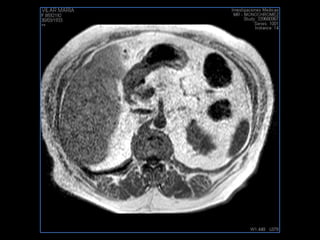

PROTOCOLO abdomen COR T2, AXIAL supresion grasa AX T1 +SAG T2  CON   GADOLINIO :  COR T1+AX T1(DIN) SAT: NO  FASE: RL THK: 6MM  COIL:  GAP: (FACTOR 1.4) 2MM FOV: 40 CM NEX:2 SINCRONIZACION RESPIRATORIA EN 3 O 4 CICLOS ALE

resonancia de abdomen